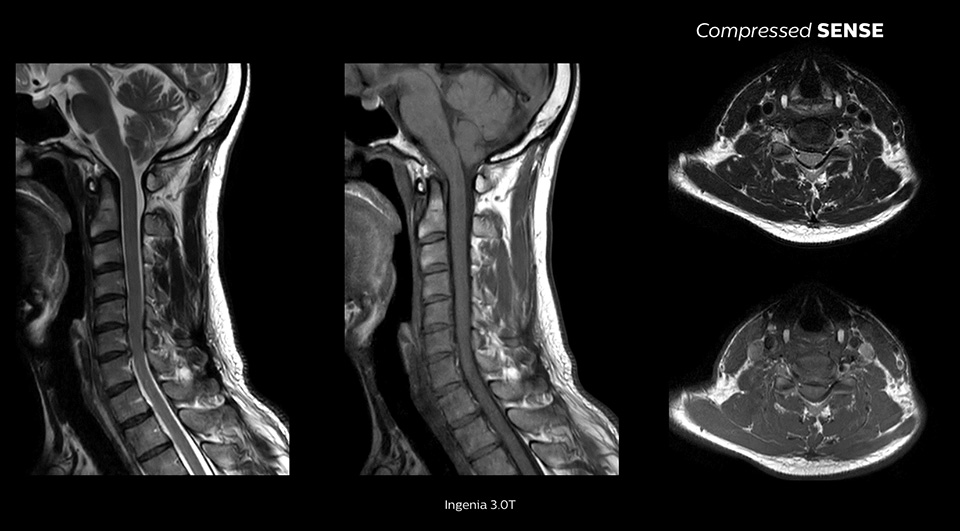

We are essentially running our standard protocols and just turning Compressed SENSE on and seeing a 20% reduction in scan time. None of the physicians know if it’s a Compressed SENSE scan versus a non-Compressed SENSE scan when they’re reading."

John P. Karis, M.D. Director of MRI and brain imaging, Department of Neuroradiology at Barrow Neurological Institute, USA

Enables up to 64% improvement in spatial resolution1

Today we can go for that high resolution again because it becomes feasible with Compressed SENSE."

Dr. Jan W. Casselman, MD, PhD, Chair of Department of Radiology, A.Z. Sint-Jan Hospital, Bruges, Belgium and Head & Neck “Consultant Radiologist,” A.Z. Sint Augustinus Hospital, Antwerp, Belgium